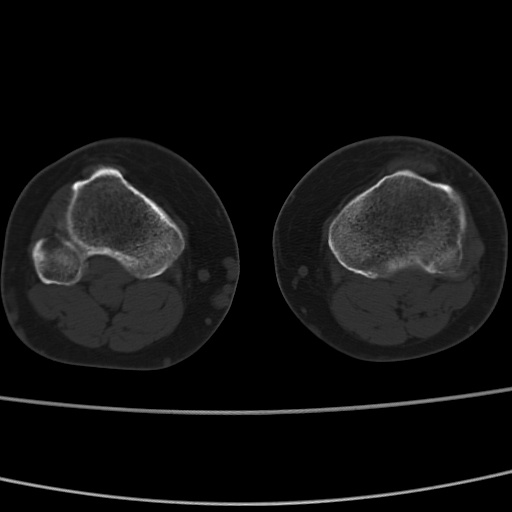

女性,50岁。【请提供患者临床症状体征】

右膝关节退行性改变,关节游离鼠。

右膝关节退行性改变,滑膜黏液囊钙/骨化并游离。